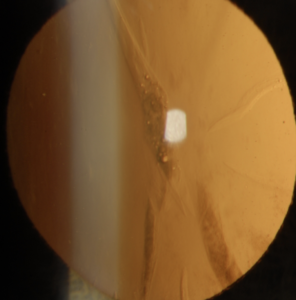

A cataract occurs when the lens inside the eye loses its clarity, resulting in blurred vision. Worldwide, this is still the most common cause of blindness.